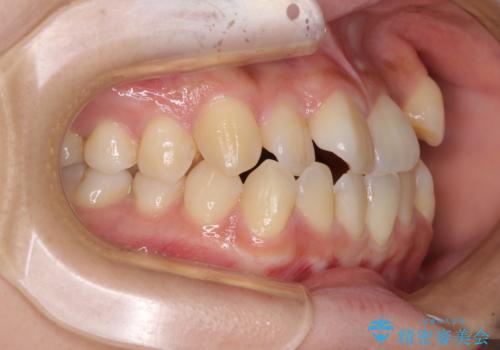

- 八重歯や前歯の捻転とクロスバイトが気になり、インビザラインによる矯正治療を希望して来院された患者様です。

上顎側切歯(上の真ん中から2番目の歯)が舌側転位している場合、無理して動かそうとすると歯髄壊死を起こすリスクが高い印象があります。

インビザライン単体でも治療は可能ですが、安全策としてインビザラインで歯列を移動する前に上顎前歯をワイヤー矯正で整え、その後上下歯列をインビザラインにて矯正治療を行うこととしました。

舌側転位している側切歯特有の、切縁の位置が不揃いであったり、根元が内側に引っ込んだ状態であったりという、インビザライン独特の仕上がりになることなく、きれいに整った歯列とすることができました。